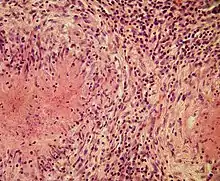

Structurally, epithelioid cells (when examined by light microscopy after stained with hematoxylin and eosin), are elongated, with finely granular, pale eosinophilic (pink) cytoplasm, and central, ovoid nuclei (oval or elongate), which are less dense than that of a lymphocyte.[4] They have indistinct shape and often appear to merge into one another, forming aggregates known as giant cells. When examined by transmission electron microscopy in epithelioid cells in the field of Golgi lamellar complex are taped not only zonated, but also sleek vesicles with dense center, and also great many (more than 100) large granulas with diameters up to 340 nm and with finegranular matrix more light than in macrophage granulas, sometimes with perigranular halo. “The most prominent feature of these cells is the enormous Golgi area; up to 6 individual stacks of Golgi cisternae may be present as well as a few bristle-coated and numerous smooth vesicles”.[5][4] Epithelioid cells have tightly interdigitated cell membranes in zipper-like arrays that link adjacent cells.[3] This cells are central in the formation of granulomas, which are associated with many serious diseases.[4] In granulomas, epithelioid cells perform the functions of delimiting.[3]

Epithelioid cells are an essential characteristic of epithelioid cell granulomas.[10] Epithelioid cell granuloma can be defined as specifically and structurally organized collection of epithelioid cells, macrophages, lymphocytes and dendritic cells. Foreign-body granulomas may be considered an organized collection of macrophages, including mere collections of giant cells surrounding inert substances like suture material – the so-called "non-immune granulomas." Granuloma formation is associated with pathogens that have learned to evade the host immune system by various means like resisting phagocytosis and killing within the macrophages. Indigestibility of matter by macrophages is a common feature of granulomatous inflammation.[4] Granulomas try to wall off these organisms and prevent their further growth and spread. Historically widespread and destructive diseases such as tuberculosis, leprosy and syphilis are granulomatous conditions. Granuloma formation is also the feature of many more contemporary conditions, like fungal infections, sarcoidosis and Crohn's disease.[4]